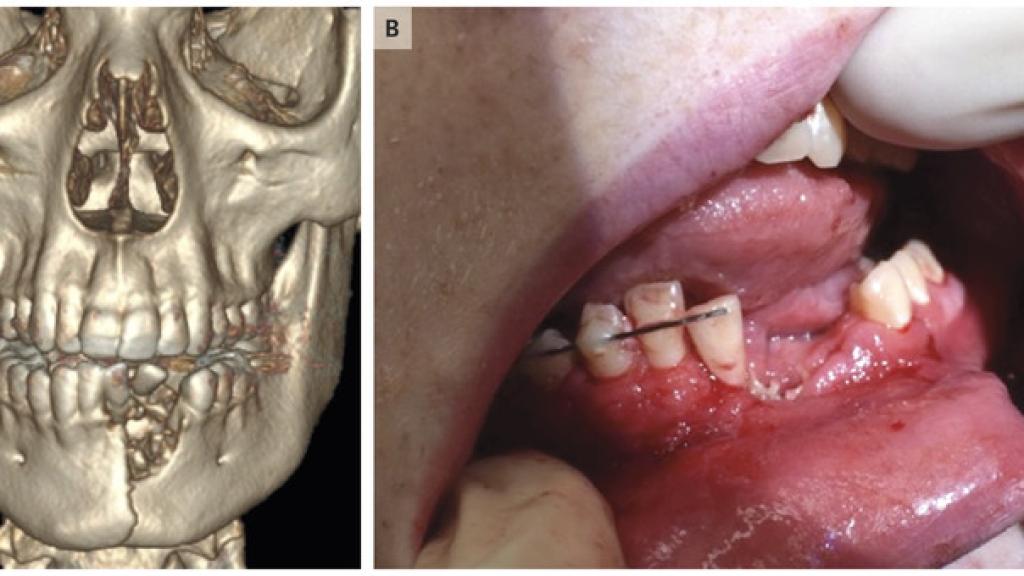

Imágenes de la boca del joven difundidas por The New England Journal of Medicine.

El chico de 17 años tuvo que recorrer más de 400 kilómetros desde una pequeña localidad de Nevada (Estados Unidos) para ser atendido en el hospital pediátrico de Utah. Tras explotarle el cigarrillo en la boca, acudió al centro hospitalario con fuertes dolores e hinchazones en la boca. Tenía cortes, quemaduras y varios dientes partidos. Además, un escáner en tres dimensiones reveló que se había fracturado la mandíbula, perdiendo una cantidad considerable de masa ósea.

Los médicos le operaron de urgencia, le colocaron una placa y un dispositivo para aguantarle los dientes mientras le soldaban la mandíbula. Ahora, el joven se ha recuperado de los daños y está pendiente de hacerse unos implantes con los que recuperar los dientes que perdió.